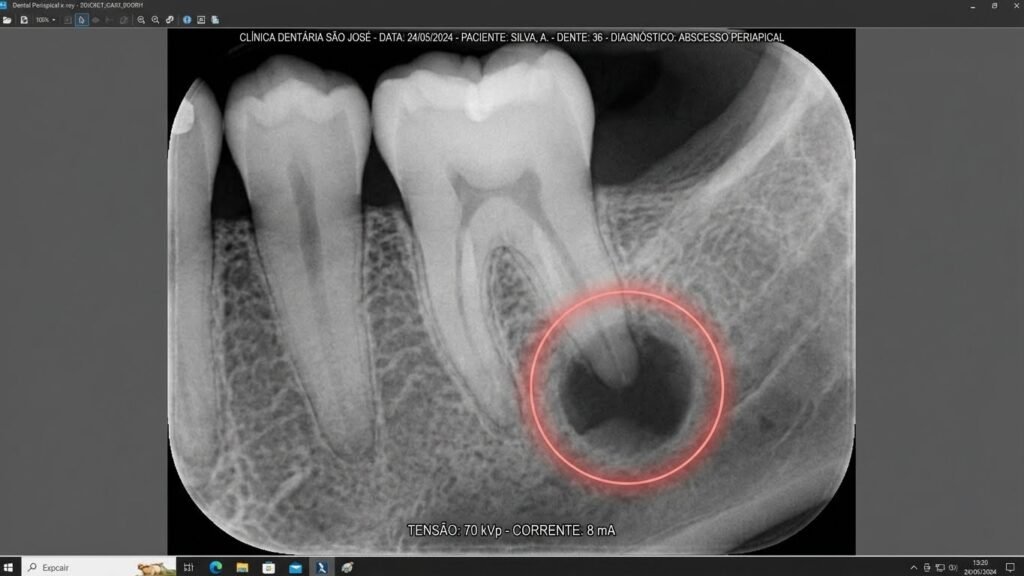

4. Presença de Pus (Abscesso Dentário)

Um abscesso é uma bolsa de pus que se forma na raiz do dente como resultado de uma infecção bacteriana. Ele pode se manifestar como uma pequena bolha na gengiva, semelhante a uma espinha. Se o abscesso se romper, pode haver um gosto ruim na boca e um alívio temporário da dor, mas a infecção ainda está presente e precisa de tratamento urgente.